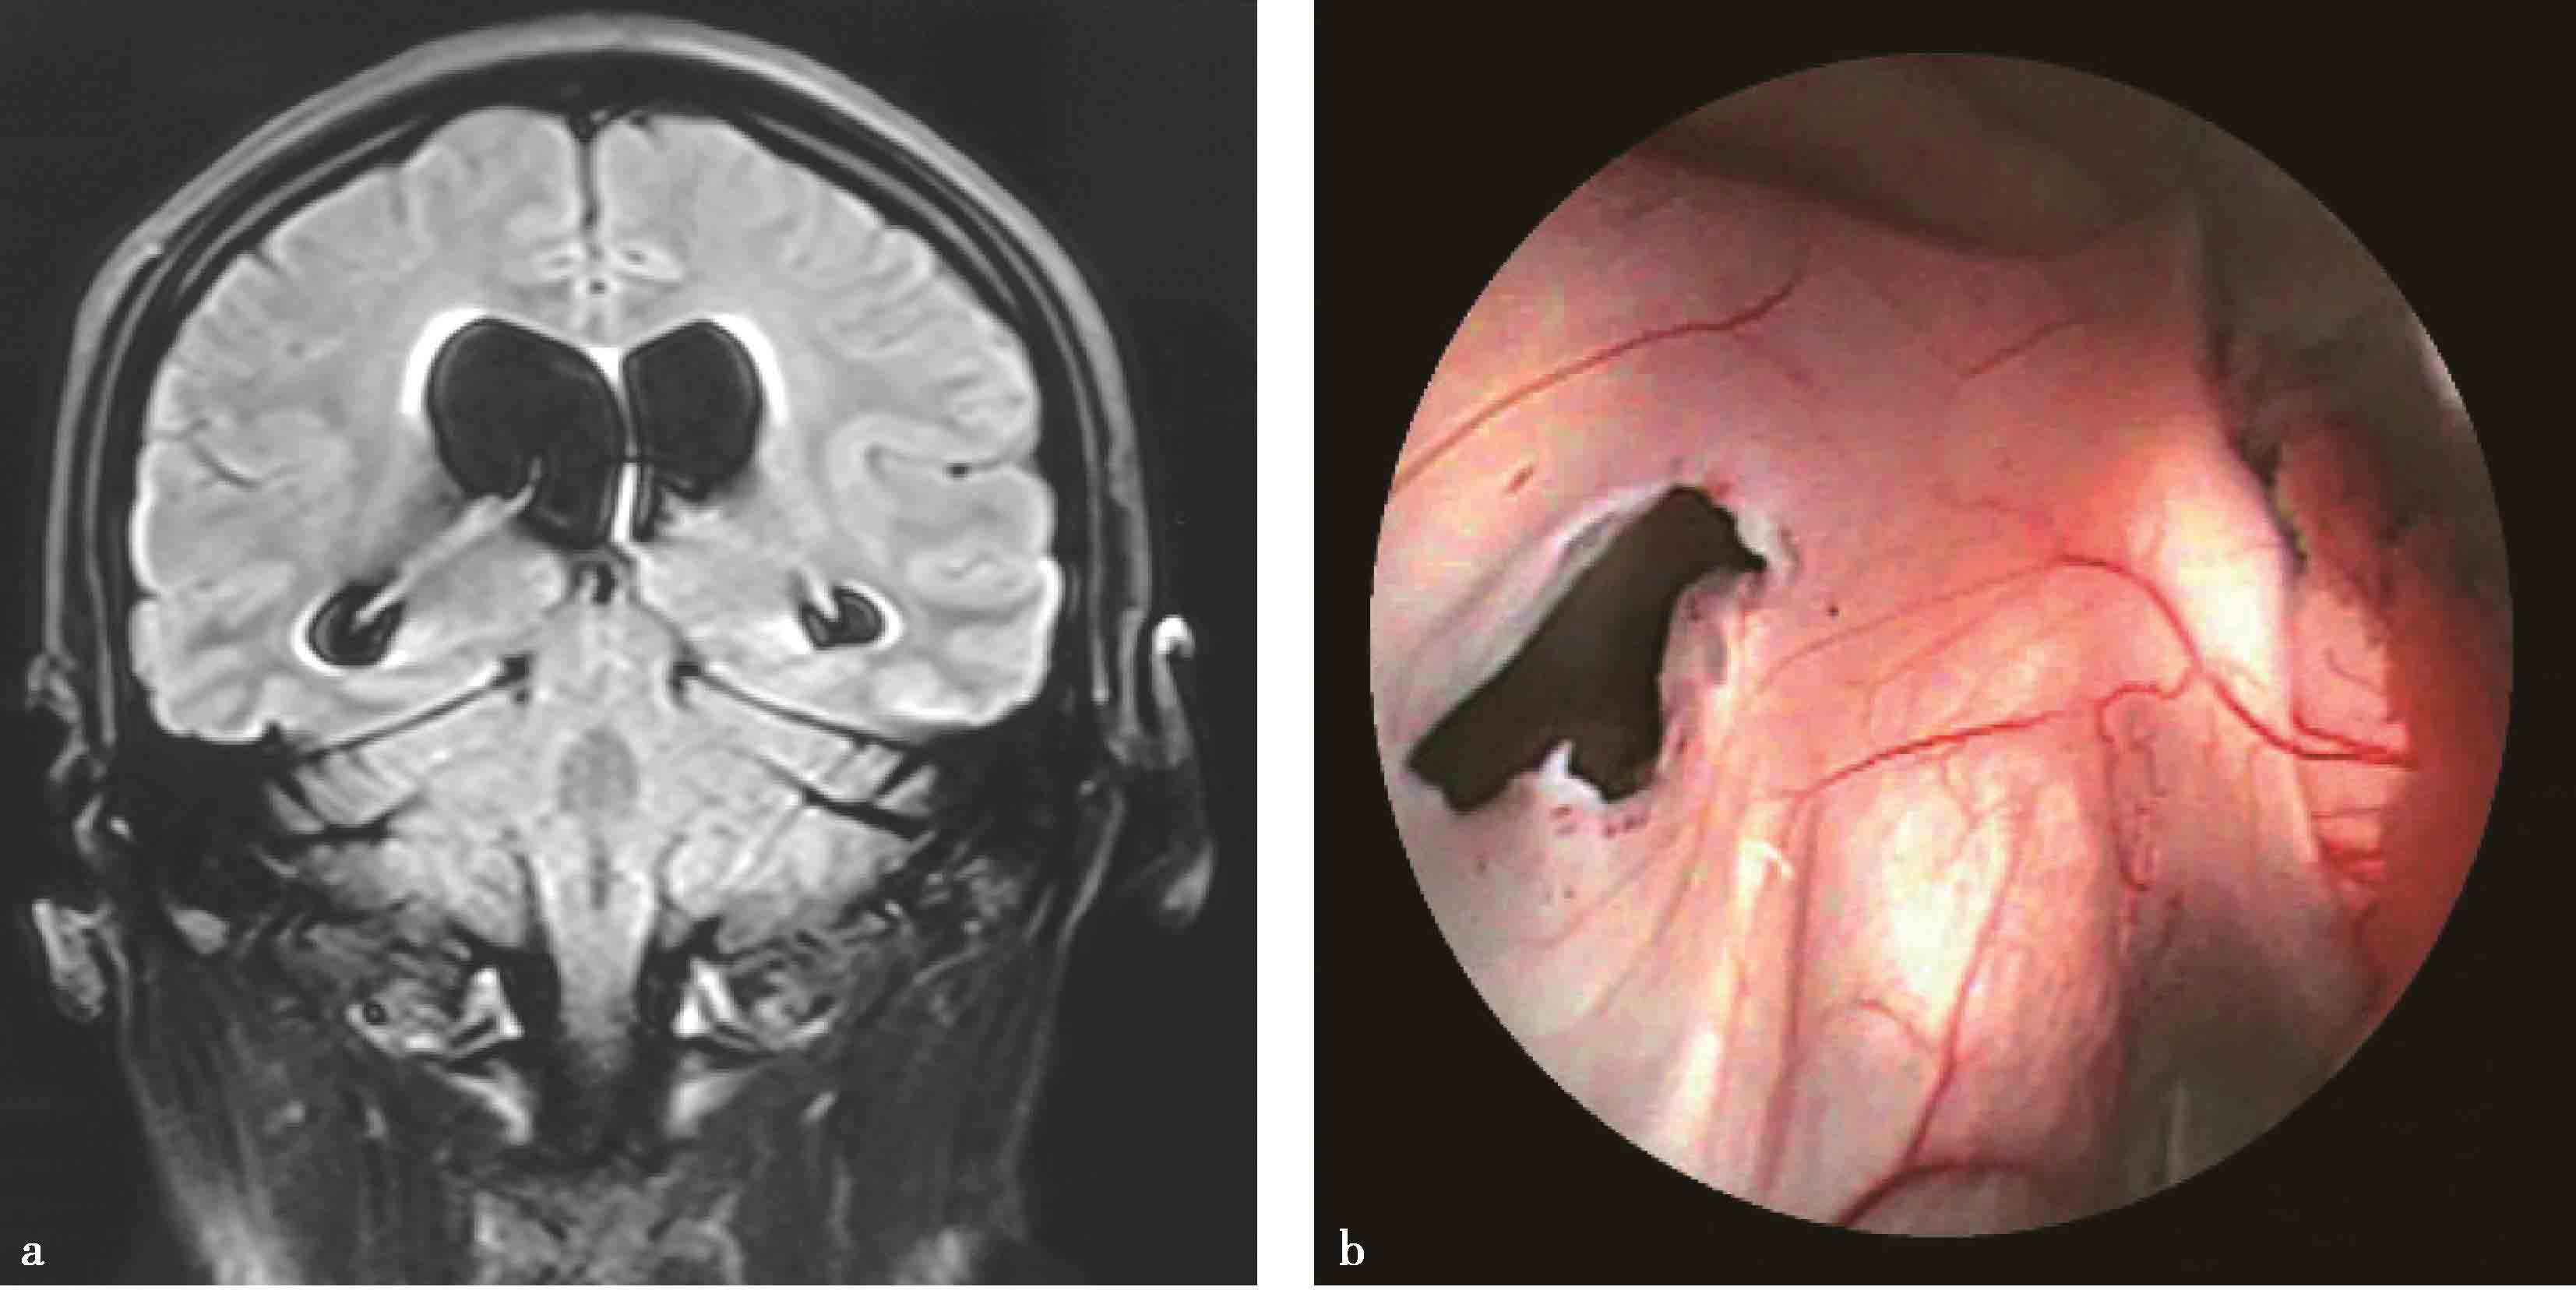

11.蛛网膜囊肿相关性脑积水的内镜治疗 蛛网膜囊肿相关性脑积水(hydrocephalus associated with arachnid cyst)的最佳治疗,是一次性同时解决囊肿和积水问题。如不能同时解决,应首先处理囊肿,禁忌单纯行脑室腹腔分流术,否则会加速囊肿增大(图3-1-2-12)。内镜下微创手术治疗,可为多数患者一次性处理囊肿和积水(图3-1-2-13)。

图3-1-2-12 蛛网膜囊肿相关性脑积

a.脑积水合并中颅窝蛛网膜囊肿及鞍上池囊肿;b.分流手术后囊肿明显增大,中线移位;c.内镜下探查见囊肿突入侧脑室;d.内镜下脑室-脑池-囊肿造瘘术,清晰显示基底池